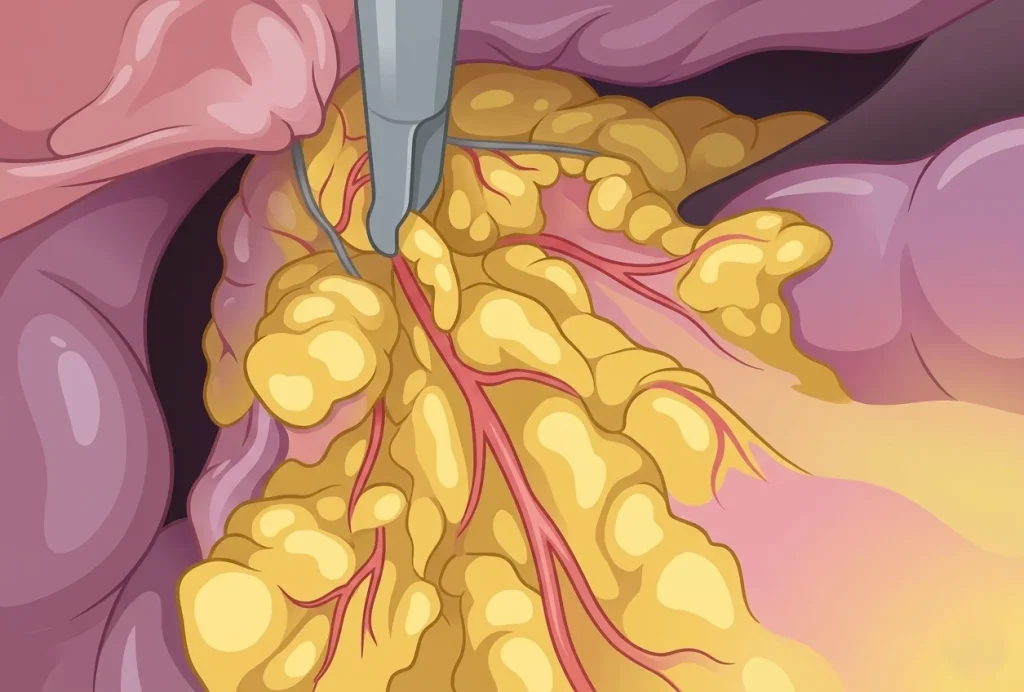

Παρακάτω παραθέτουμε εικόνες από λαπαροσκοπικό χειρουργείο μας. Τα χειρουργικά στάδια είναι η εκτομή του συριγγίου, η συρραφή του κόλπου και της ουροδόχου κύστης και η τοποθέτηση εντερικού λίπους (επίπλουν) μεταξύ κόλπου και κύστης για την καλύτερη επούλωση και μείωση των υποτροπών.